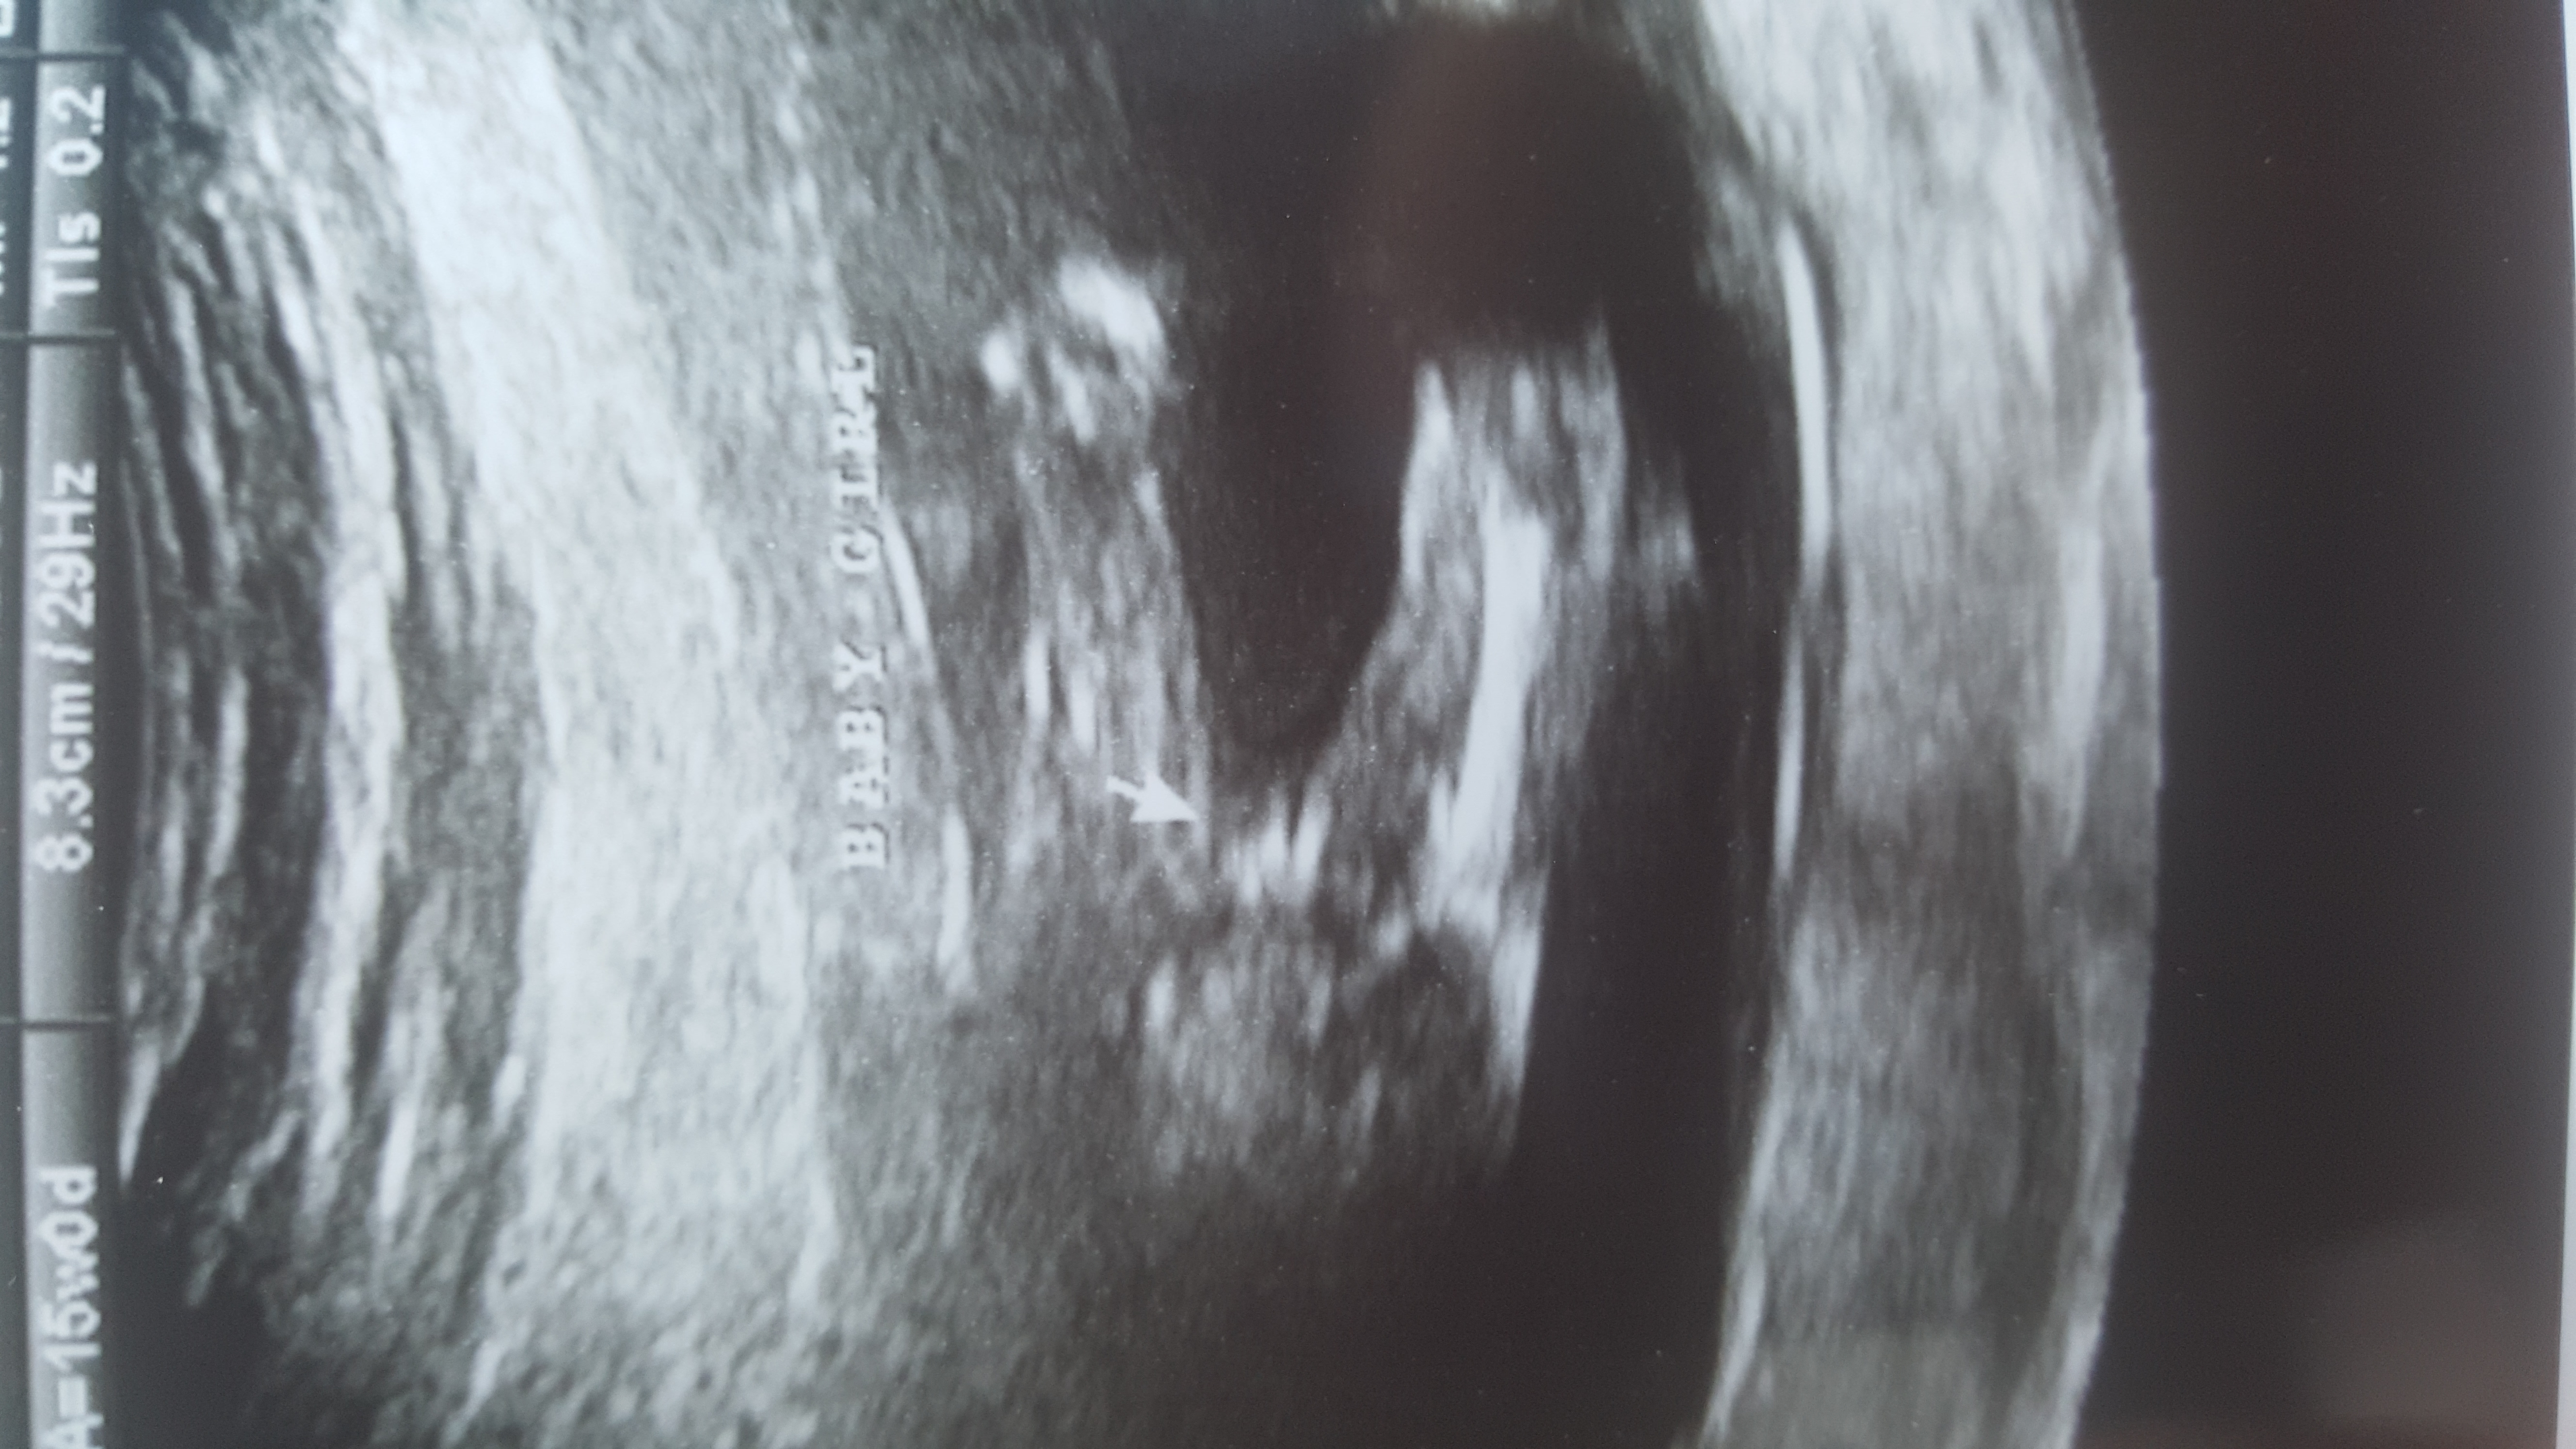

Any nub, skull or ramzi theories? I hope it's okay to create a new thread. Thank you so much in advance! :running:

13w2d:

6w: (transvaginal- done at the same office with my son and he was on the opposite side so i'm very curious! I suck at ramzi..)